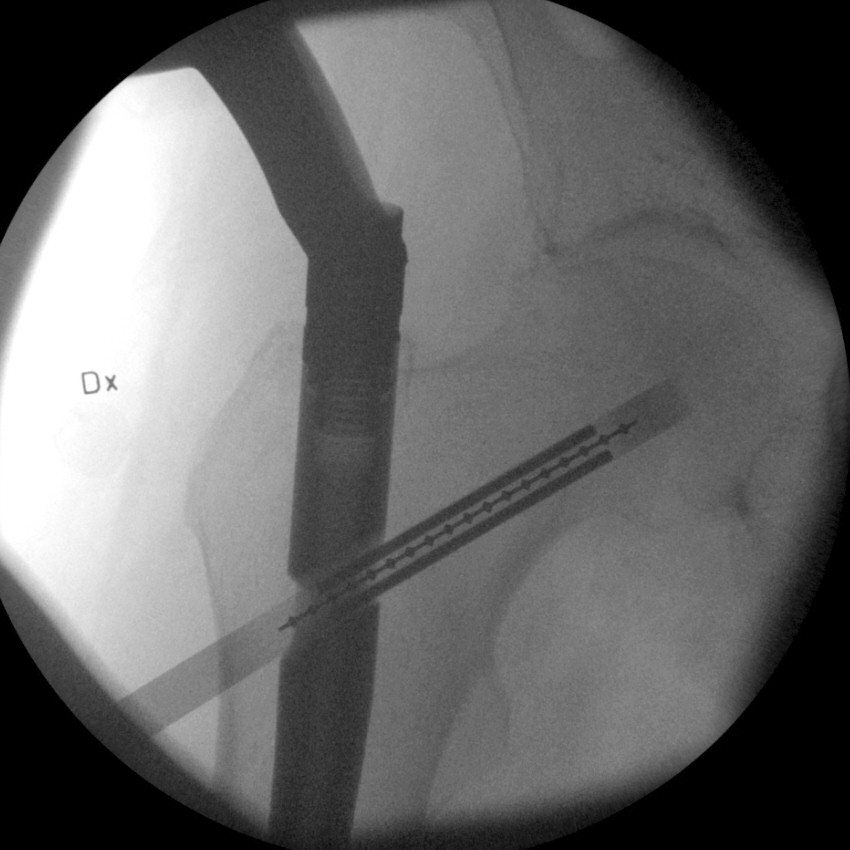

- Vrid mallen ca 90°. Titta i sidovy. Vrid spiken och justera mallen så den passerar märgspikena hål för glidskruven och hamnar motsvarande centralt i kollum och kaput.

Sidobild, mall i genomlysning, märgspikens glidskruvshål markerat med röd cirkel